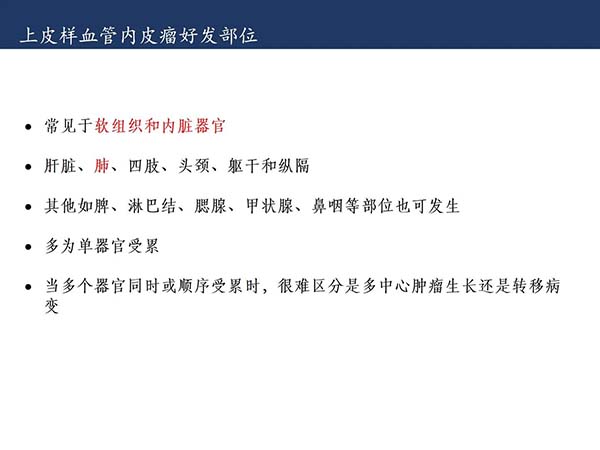

【杨柳科普】肺上皮样血管内皮瘤的影像表现